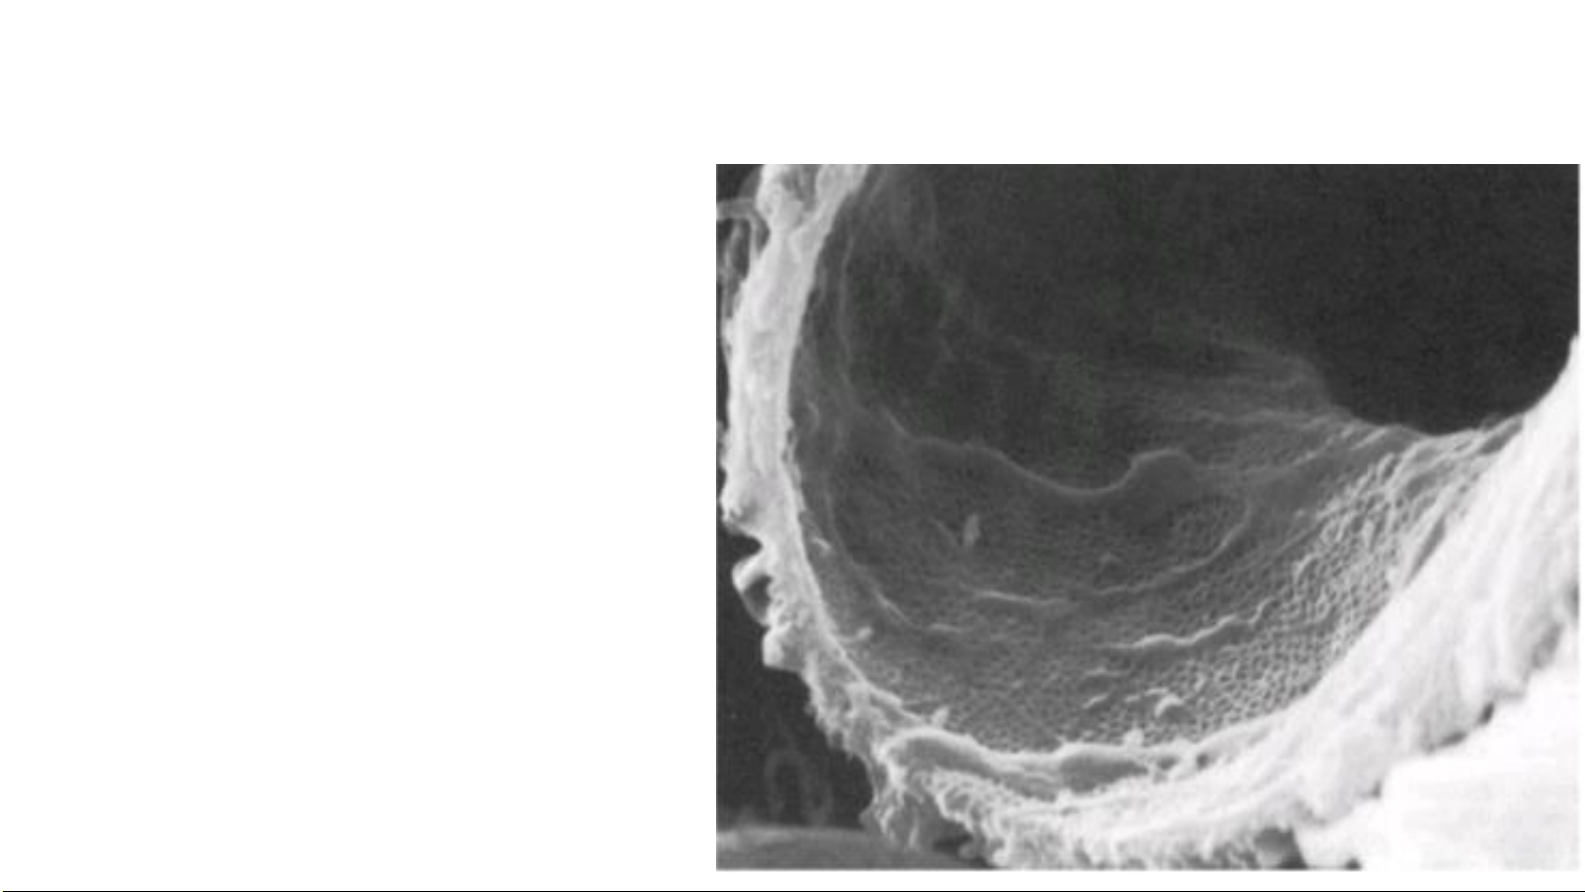

Histology and cell biology Abraham 4th Tb có chân 20

Junqueira's Basic Histology Text and Atlas 14e Tế bào có chân • Thân • Nhánh chính (1) • Nhánh thứ cấp (2) 21

Histology_ A Text and Atlas_ With Correlated Cell an Molecular Biology • Khe lọc: khoảng cách giữa các nhánh thứ cấp # 25nm B • C Màng khe lọc: 6nm màng nối các nhánh thứ phát A F E A: tb nội mô B: tb có chân C: khe lọc D: màng khe lọc E: lổ thủng tb nội mô D F: màng đáy 23